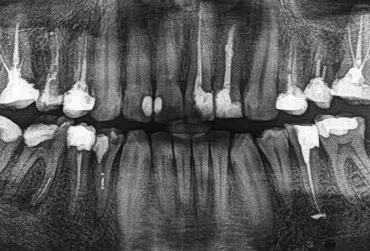

Powtórne leczenie kanałowe z pomocą AI. Czy sztuczna inteligencja może pomóc w codziennej pracy?

Artykuł przedstawia przebieg powtórnego leczenia kanałowego górnego trzonowca z pominiętym kanałem MB2 przy asyście sztucznej inteligencji.